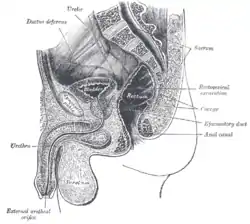

The interior of the anal canal and lower part of the rectum Median sagittal section of male pelvis

Median sagittal section of male pelvis Median sagittal section of female pelvis

- Anatomy figure: 44:05-00 at Human Anatomy Online, SUNY Downstate Medical Center — "The rectum and anal canal in the male pelvis"